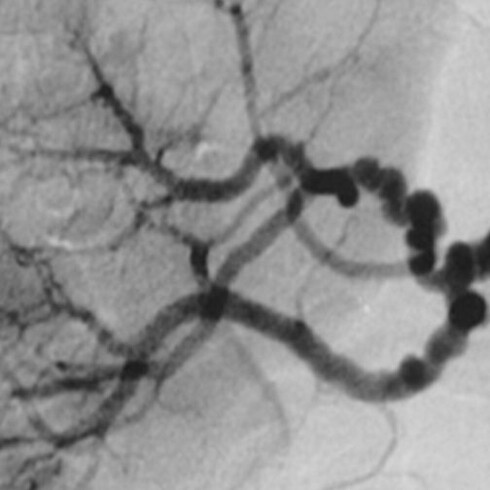

A Dios gracias, eso faltaba a la verdad. Cuando el cirujano doctor lo describió, me alegré. Un aneurisma es una falla congénita que puede suceder a cualquier edad. Es difícil de sanar, toma tiempo (mucho tiempo) y yo no contaba con ese preciado tesoro a mis 64 años.